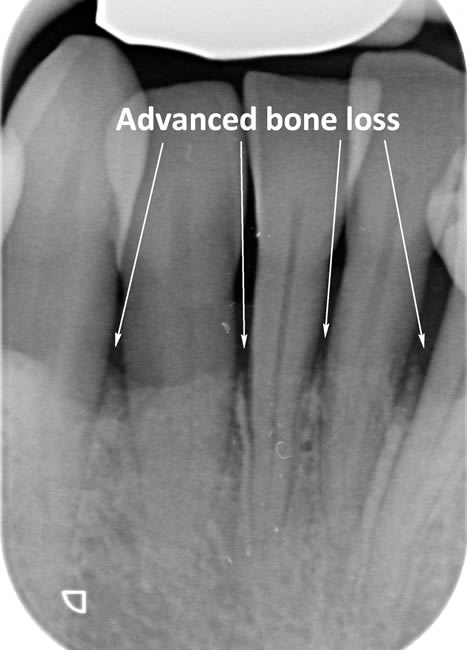

Periodontitis is a more advanced stage of gum disease where there has been damage to the bone which supports the teeth. If left untreated periodontitis leads to more and more bone loss until the teeth start to become loose and eventually fall out by themselves or need to be extracted by a Dentist.

The main cause of gum disease is plaque. Plaque consists of millions of bacteria which live on and around the teeth and gums. These bacteria produce toxins which damage the gums. To begin with the gums start to peel away from the teeth and “pockets” form. As the bacteria penetrate deeper into these “pockets” they then start to cause damage to the bone which holds the teeth in. As more bone loss occurs the teeth start to become increasingly looser until they eventually start to fall out one by one.

The diagrams below show the different stages of gum disease